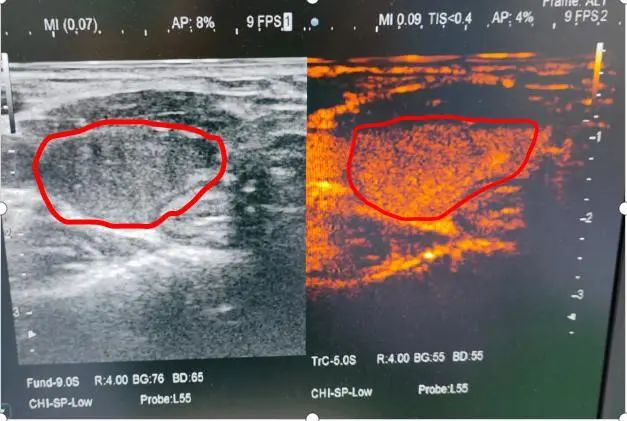

甲亢消融前造影提示肿大甲状腺